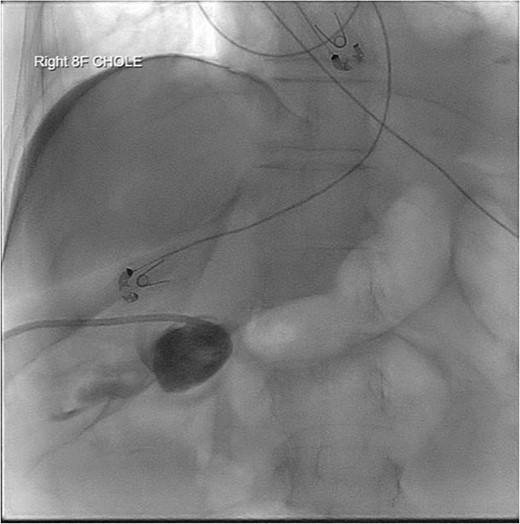

Given her surgical history, duration of symptoms, and active chemotherapy, she was deemed high-risk for intraoperative biliary injury and poor wound healing. Cholecystectomy was deferred and the gallbladder was decompressed with PCT placement. The patient demonstrated significant symptomatic improvement, diet was advanced, and she was discharged home on hospital Day 5. Several hours after discharge, she returned due to lethargy and was found to be in septic shock. Repeat imaging revealed a dislodged PCT. She was admitted to the surgical intensive care unit (ICU) for vasopressor support and mechanical ventilation. Cholangiogram was performed and revealed the pigtail catheter in the peritoneal space (Fig. 2). Under fluoroscopic guidance, the pigtail catheter was replaced without difficulty. She was started on antibiotics for bacteremia and remained in the ICU for management of septic shock and acute hypoxic respiratory failure.

PCT check using fluoroscopy showing retracted tube in the peritoneal fluid.